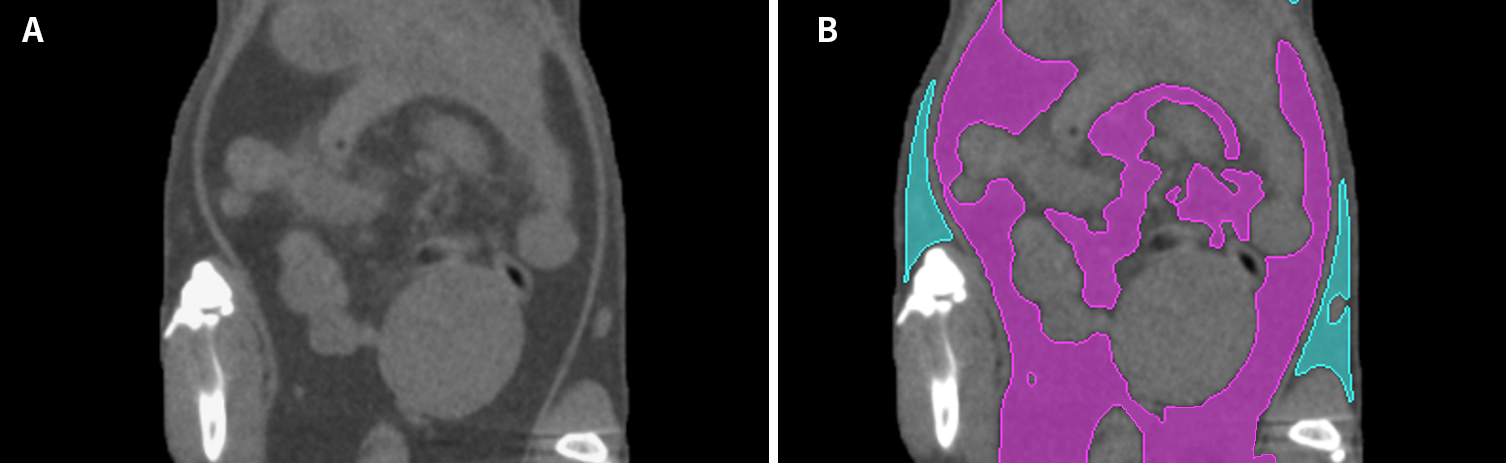

图一:小鼠腹部显微CT图像

图二:A)小鼠腹部Micro-CT二维矢状面;B脂肪分割分离并分类,皮下脂肪显示为色,内脏脂肪显示为色。